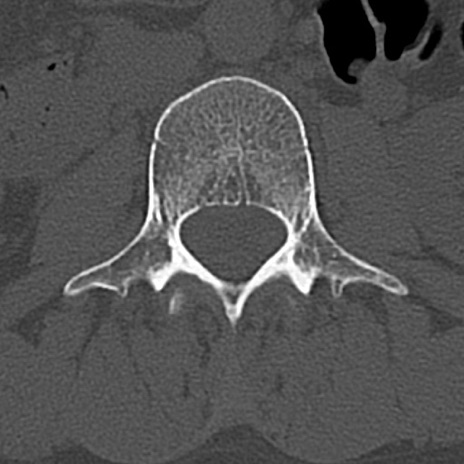

【整形】TIPS症例4 腰椎CT(横断像)

腰椎CT

横断像と矢状断像